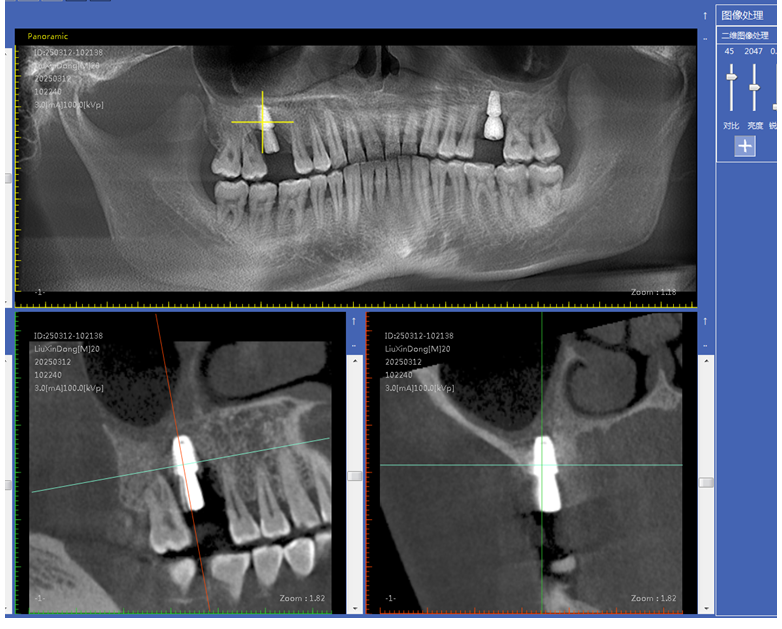

即刻种植与即刻修复技术:在拔牙后立即将种植体植入拔牙窝内,并在种植体植入后短期内(通常在数天至数周内)完成牙冠修复。这种技术可以减少患者缺牙的时间,避免牙槽骨因缺牙而发生吸收,同时能够更快地恢复患者的咀嚼功能和美观。

骨增量技术:对于牙槽骨骨量不足的患者,采用骨增量技术来增加骨量,以满足种植牙等手术的需求。常见的骨增量技术包括引导骨组织再生术(GBR)、上颌窦提升术、骨劈开术等。这些技术通过使用生物材料和特殊的手术方法,促进牙槽骨的再生和修复,扩大了种植牙的适应证,使更多患者能够接受种植修复。

数字化导板技术:通过口腔 CT 扫描获取患者口腔颌骨的精确三维数据,利用计算机辅助设计(CAD)和计算机辅助制造(CAM)技术制作出个性化的手术导板。在牙槽外科手术中,如拔牙、种植牙等,导板可以精确引导手术器械的操作,提高手术的准确性和可预测性,减少手术创伤和并发症,同时缩短手术时间。